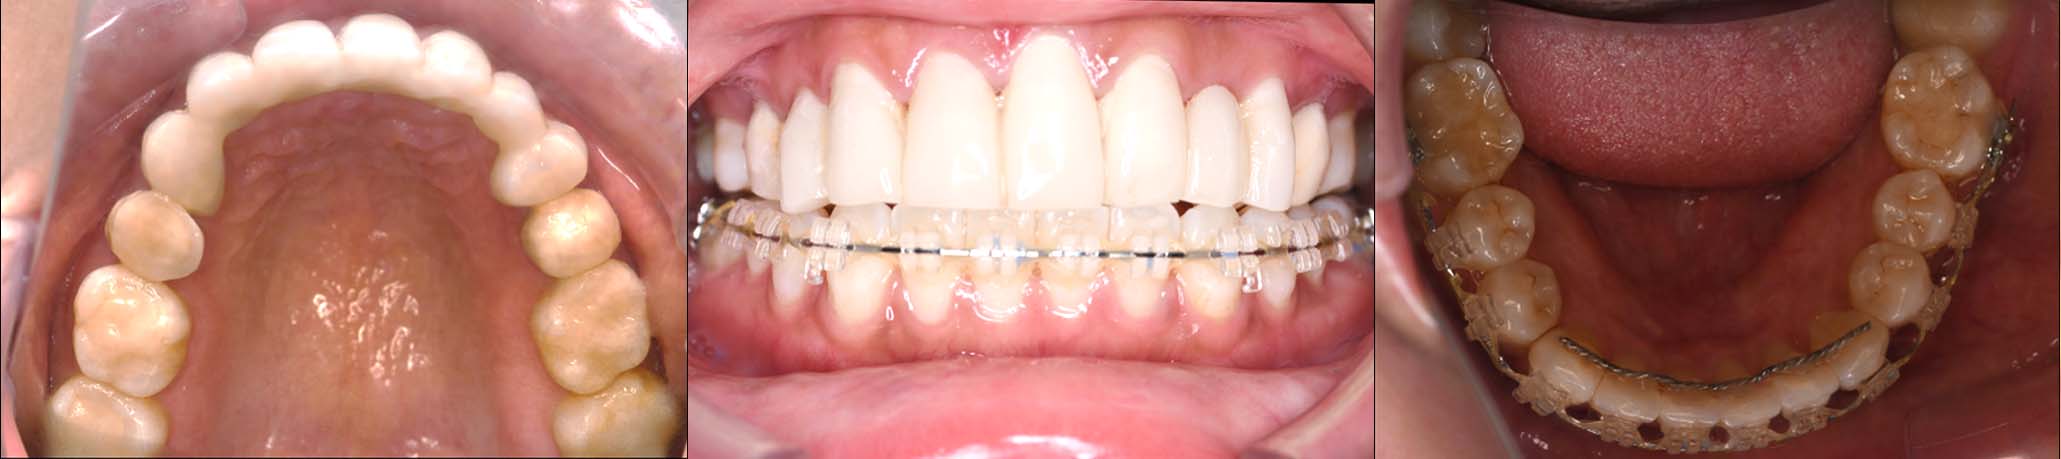

| 治療内容 | ①スプリントを装着 ②副子を装着 ③2024年4月 口腔内反映開始 ④副子を入れた状態の所まで咬合を挙上 (バイトアップ) ⑤2024年5月 上顎前歯部8本へ仮歯(TEK) を装着 |

バイトアップ後